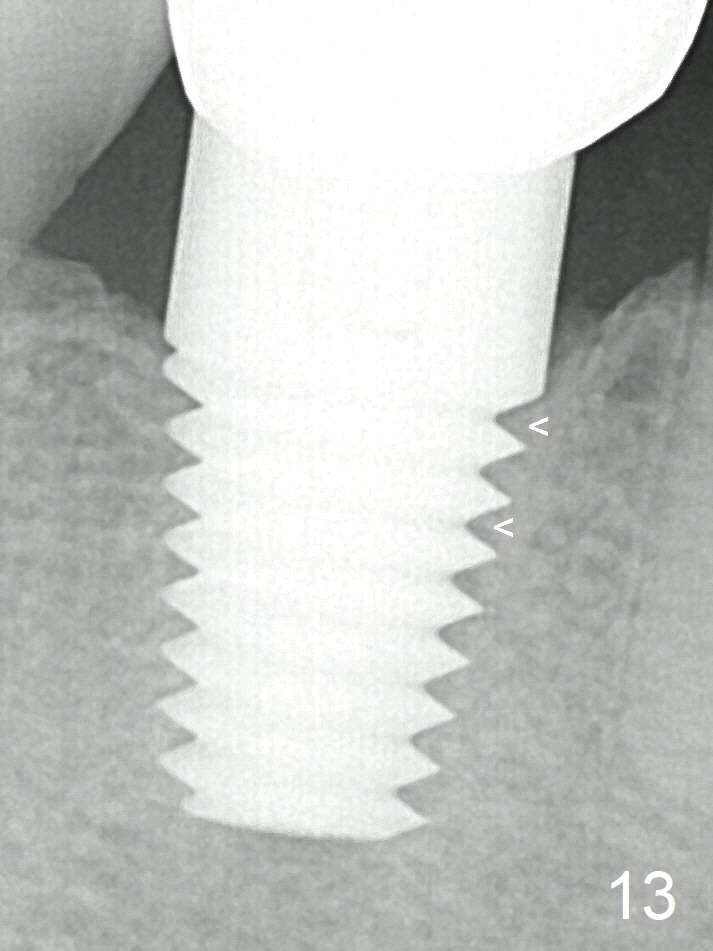

Cortex-like bone seems to have grown into the mesiocoronal thread spaces 3 years post cementation (Fig.13 <).